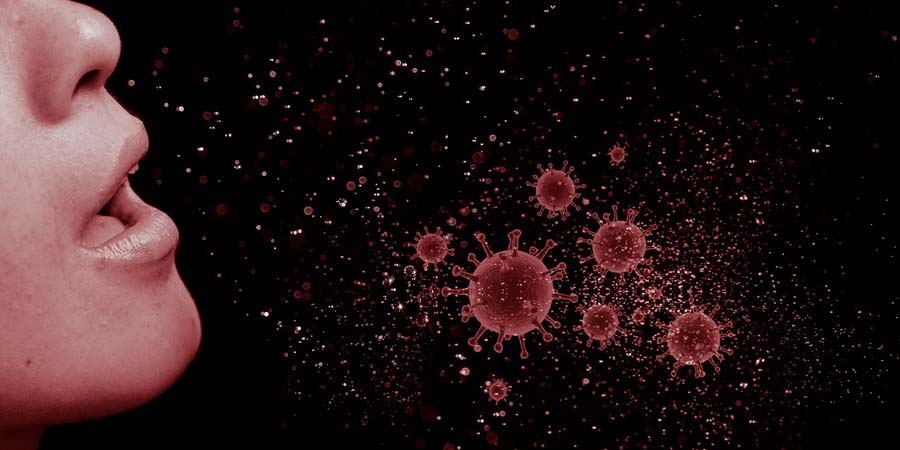

В Саратовской области за сутки коронавирус унес жизни 20 человек

В Саратовской области за сутки от коронавируса умерло еще 20 человек. Об этом «Четвертой Власти» сообщили сегодня, 16 сентября, в региональном министерстве здравоохранения.

Среди умерших 13 женщин и 7 мужчин в возрасте от 58 до 95 лет. Таким образом, за время пандемии в регионе от коронавируса скончалось 2640 саратовцев.

Напомним, за сутки в Саратовской области обнаружили еще 251 больного коронавирусом.